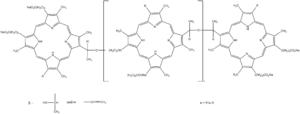

Sonosensitizers, or sonosensitizing therapeutics, are the primary element of SDT and can be tailored to treat various cancers and generate different effects.[2] These therapeutics, often involving the use of porphyrin or xanthene, will initiate a toxic effect via the ROS upon exposure to ultrasound.

Porphyrin-based sensitizers

Porphyrin-based sensitizers, initially used as a photosensitizer in PDT, are fairly hydrophobic molecules derived from hematoporphyrin.[1] Single oxygen atoms or hydroxyl radicals are produced by porphyrin-based sensitizers upon exposure to ultrasound or light, providing the cytotoxic effects desired with sonodynamic and photodynamic therapies.[1] However, the result of porphyrin-based sensitizers is not as local as desired for sonodynamic therapy since they are also located in non-targeted tissue between the tumor and the ultrasound emitter.[1]

Xanthene-based sensitizers

Xanthene-based sensitizers, on the other hand, have shown successful cytotoxicity in vitro by producing reactive oxygen species after being triggered by ultrasound.[1] More research is necessary to improve its potential in vivo performance since it is quickly processed by the liver and cleared from the body.[1] Rose Bengal is a commonly used xanthene-based sonosensitizer.[1]

Additional sensitizers

Other sensitizers that have been investigated for their potential in sonodynamic therapy (and have also been used previously in PDT) include acridine orange, methylene blue, curcumin, and indocyanine green.[1] A study by Suzuki et al. used acridine orange, a fluorescent cationic dye that can insert itself into nucleic acids, for treating sarcoma 180 cells with ultrasound and demonstrated that reactive oxygen species are a critical element of SDT considering that their absence decreased the efficacy of SDT.[33] Similar to the previous study, a recent study by Komori et al. utilized ultrasound coupled with methylene blue (a phenothiazine dye commonly used in PDT that exhibits low toxicity) to irradiate sarcoma 180 cells and found that methylene blue was an effective sonosensitizer in decreasing cell viability.[34] Interestingly, curcumin is a spice that also can act as a sensitizer for PDT and SDT.[1] In a study by Waksman et al., curcumin was able to impact macrophages, which are important for development of plaques found in atherosclerosis patients, thus reducing the amount of plaque in an animal model.[35] These findings along with other research indicate that curcumin sensitizers could be used in SDT cancer treatments. Indocyanine green is a dye that absorbs near infrared wavelengths and is another sensitizer that has been shown to reduce cell viability when coupled with ultrasound and/or light.[36] An in vivo study demonstrated that treating a mouse tumor model with indocyanine green coupled with ultrasound and light resulted in a 98% reduction in tumor volume by 27 days after treatment.[36]